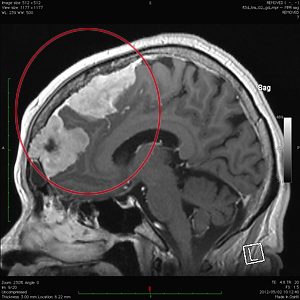

良性腫瘍の手術前

手術後